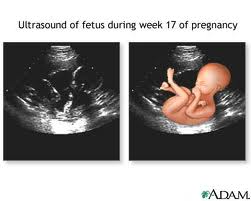

УЗИ при беременности — варианты и норма

Как не странно для обычных пациентов, УЗИ при беременности бывает разное, и речь идет не об оборудовании или опыте врача. Существует три типа проведения УЗИ во время беременности: Стандартный, Фундаментальный и Экспертный. Не стоит путать со скрининговыми методами и т.д.

Как не странно для обычных пациентов, УЗИ при беременности бывает разное, и речь идет не об оборудовании или опыте врача. Существует три типа проведения УЗИ во время беременности: Стандартный, Фундаментальный и Экспертный. Не стоит путать со скрининговыми методами и т.д.

Обычному пациенту довольно трудно разобраться во всех типах УЗИ при беременности, особенно если ему и не предлагают выбор. Самым базовым уровнем обследования, который проводят 90% клиник Украины это Стандартное Ультразвуковое исследование плода.